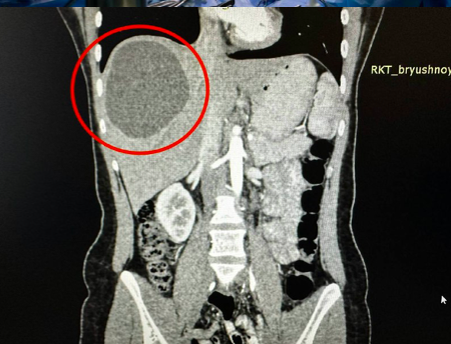

В Республиканской клинической больнице (РКБ) хирурги извлекли из печени 19-летней девушки огромный ком паразитов. Об этом сообщили в Telegram-канале медицинского учреждения. Пациентка жаловалась на сильные боли в животе. Во время обследований у неё обнаружили паразитов в печени. Они образовались в органе кисту размером 20 на 15 сантиметров. Сначала девушке назначили химиотерапию, чтобы убить паразитов, а потом сделали операцию. — Из-за того, что паразиты поразили здоровые ткани печени, хирургам пришлось убрать практически треть органа, — говорится в сообщении. Операция длилась 2,5 часа. Сейчас пациентка идёт на поправку. Ранее сообщалось, что в Австралии из мозга женщины достали живого 8-сантиметрового червя. Фото: А42.RU, РКБ/Telegram

Пациентка жаловалась на сильные боли в животе. Во время обследований у неё обнаружили паразитов в печени. Они образовались в органе кисту размером 20 на 15 сантиметров.